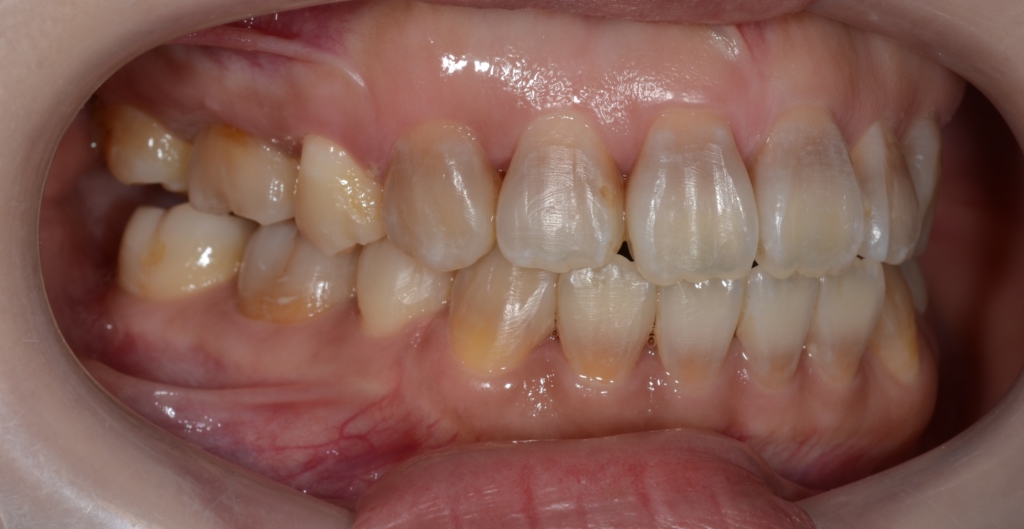

患者さんは、20代の女性(社会人)です。

「八重歯などのガタガタを治してきれいな歯並びになりたい!」

というのが一番の希望でした。

合わせて、口元が少しでも引っ込んで、お口を閉じる時にオトガイ辺りの「力」が抜けてしわが無くなればもっと嬉しい!とのことでした。

#1.顎と歯の不調和による叢生(重度)

#2.上顎前突(出っ歯)

#3.開口

と診断しました。